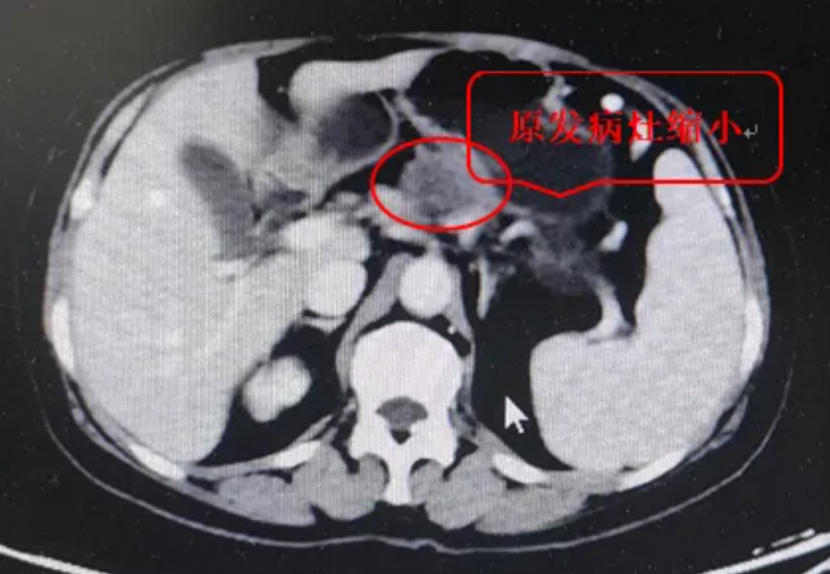

影像学检查显示胰腺体部占位,病变包绕脾动脉,肝脏多发转移瘤。病理显示是浸润性低分化腺癌,最终确诊胰体腺癌IV期。胰腺癌晚期的中位生存期一般仅有4-6个月,这位阿姨还有合并糖尿病,之前还进行过膝关节置换术,精神状态也不是很好。

住院后,我们主任针对此患者迅速召开了多学科综合治疗会议,要求延长患者生存期的同时还要保证患者的生活质量。考虑到患者的年龄(65岁)以及她爱美的心情,我们给她拟定了AG联合尼妥珠单抗(400mg)的治疗方案。于2022年8月起进行了6个治疗周期后,患者肿瘤评估PR。在化疗阶段,患者出现了1级胃肠道反应,出现II度骨髓移植,但治疗后均缓解,CA199也明显下降。

患者后续于2023年1月起又进行了6个周期的维持治疗,疗效评价PR且没有出现任何不良反应,患者的精神状态和饮食等都非常好。